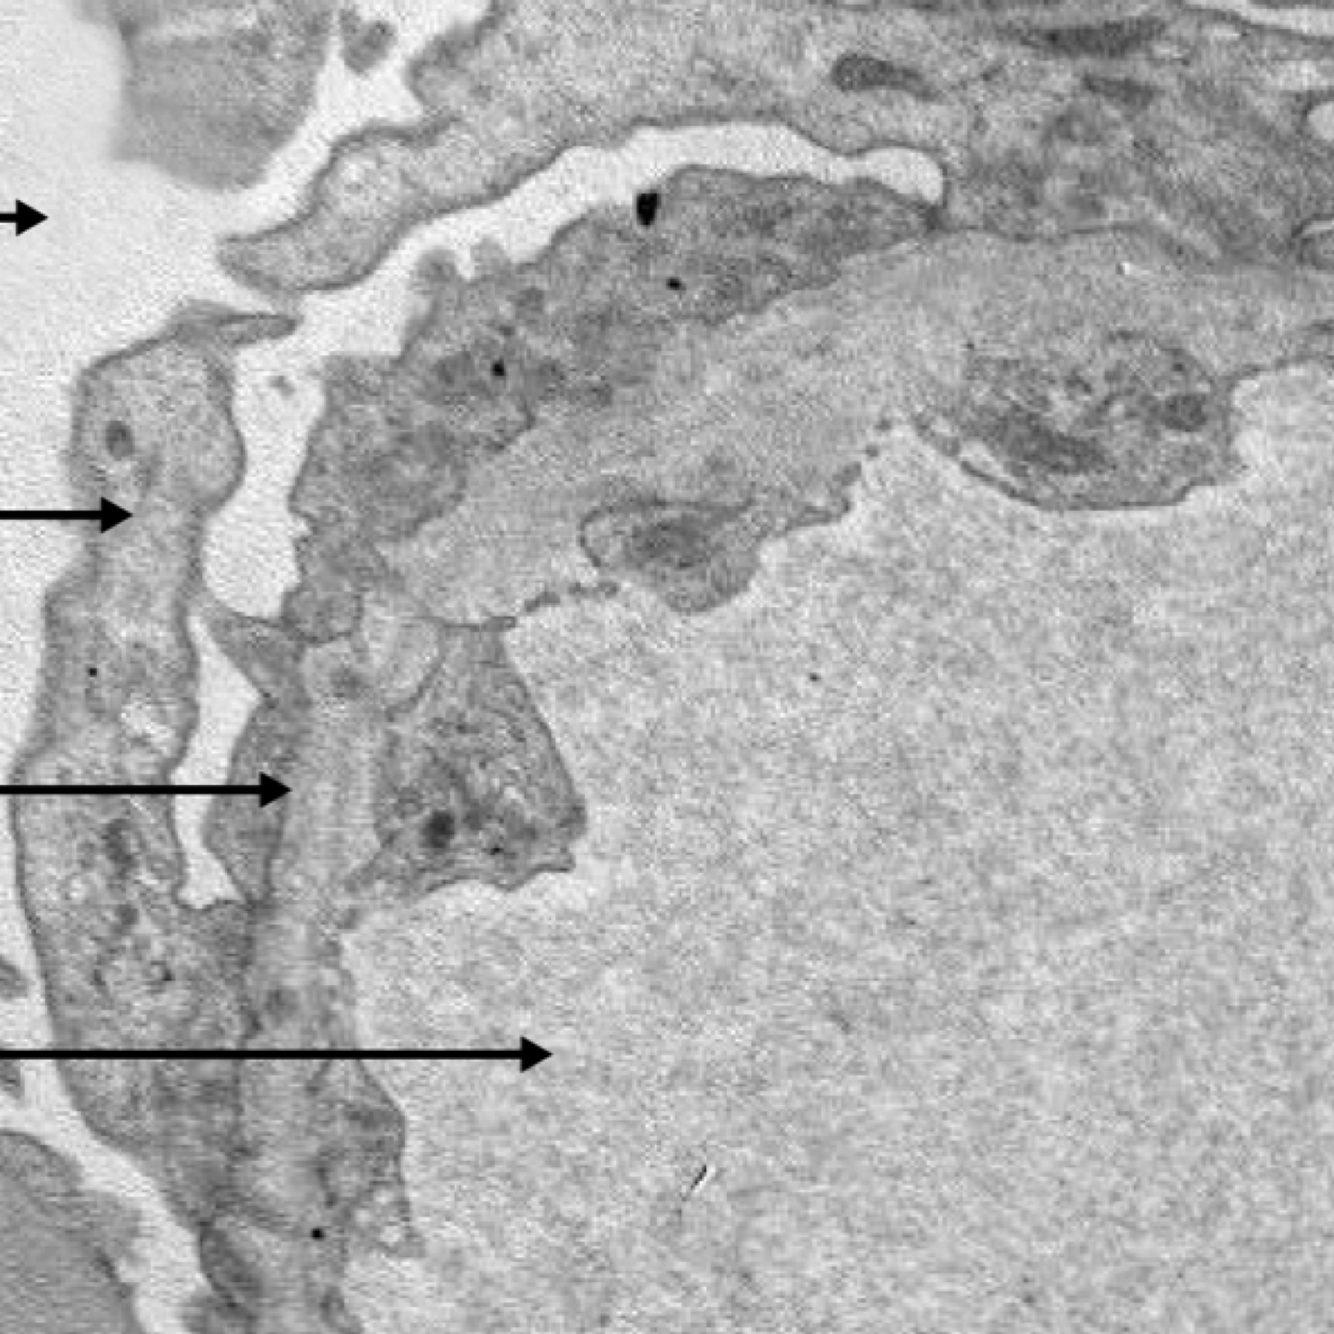

focal segmental glomerulosclerosis (FSGS)